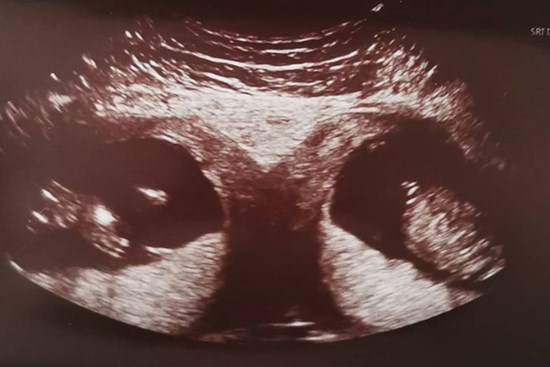

Kỳ lạ mẹ bầu mang song thai, nhưng là trong 2 tử cung khác nhau

Đây đúng là trường hợp mang thai có một không hai khi theo các bác sĩ, cứ 50 triệu người thì may ra mới phát hiện 1 trường hợp.

Bác sĩ cho biết đây là hiện tượng thai trong thai – một hiện tượng hiếm gặp, có thể người mẹ đã mang thai đôi.